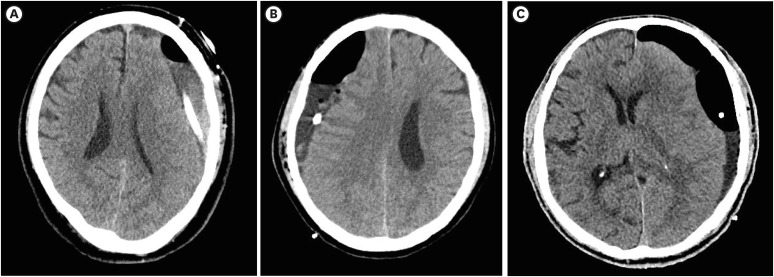

Results: Of the 370 patients, 345 (93.2%) had no recurrence and 25 (6.8%) had recurrence. Univariate and multivariate analyses revealed that male sex, advanced age, bilateral hematoma, moderate or severe brain atrophy, separation type, gradation type, and burr hole trephination were independent risk factors for CSDH recurrence.

Conclusion: Sex, age, bilateral hematoma, brain atrophy, hematoma density and architecture, and surgical techniques are all associated with CSDH recurrence.